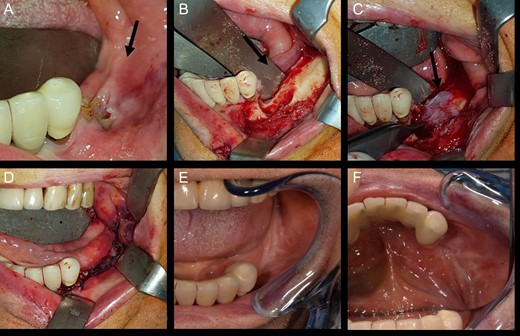

In November 2016, the patient underwent surgery under general anaesthesia. After infiltration of a local anaesthetic (mepivacaine + adrenaline 1:200 000), surgery was carried out as described: mucoperiosteal incision of the right mandible with mesial and distal drainage, extensive fistulectomy of the hyperplastic mucose membrane, which showed multiple fistulas, skeletonisation and exposure of abundant necrotic tissue; debridement of hyperplastic-inflammatory tissue and ostectomy of necrotic bone with osteoplasty of sharp edges; positioning of HAM and water and hermetic suture with Polisorb 3/0 absorbable braided thread (Fig. 2A–E). Histological examination confirmed the presence of inflammation and the diagnosis of osteonecrosis. The mesial and distal bone curettage margins were dictated by the x-ray images (Fig. 3) identifying above all the radio-opaque areas, often associated with a periosteal reaction, as well as by the need to remove any bone sequestra present. The imaging was also associated with the intraoperative assessment of the macroscopic appearance of the bone and in particular the signs of bleeding from the cortex and medulla. The HAM was 3 × 3 cm2 in size and was positioned over the curetted area and under the mucosal flap.

View of mandibular alveolar process in patient 1: (A) preoperative BRONJ affected area; (B) fistula, (C) curetted area, (D) HAM application, (E) suture of mucosal soft tissues and (F) postoperative follow-up after a period of 180 days.

The patient was submitted to a clinical and radiological follow-up 180 days after the procedure. The intraoral wound was completely sealed, the patient was asymptomatic and no further abscesses had developed (Fig. 2F).

In November 2016 the patient underwent surgery under general anaesthesia (same technique used for the first patient described) (Fig. 4A–D). The mesial and distal bone curettage margins were dictated by the x-ray images (Fig. 5) which identified above all the radio-opaque areas, often associated with a periosteal reaction, as well as by the need to remove any bone sequestra present. The HAM was 3 × 3 cm2 in size and was positioned over the curetted area and under the mucosal flap.

View of mandibular alveolar process in patient 2: (A) preoperative BRONJ affected area; (B) curetted area; (C) HAM application; (D) suture of mucosal soft tissues; (E) and (F) postoperative follow-up after a period of 180 days.